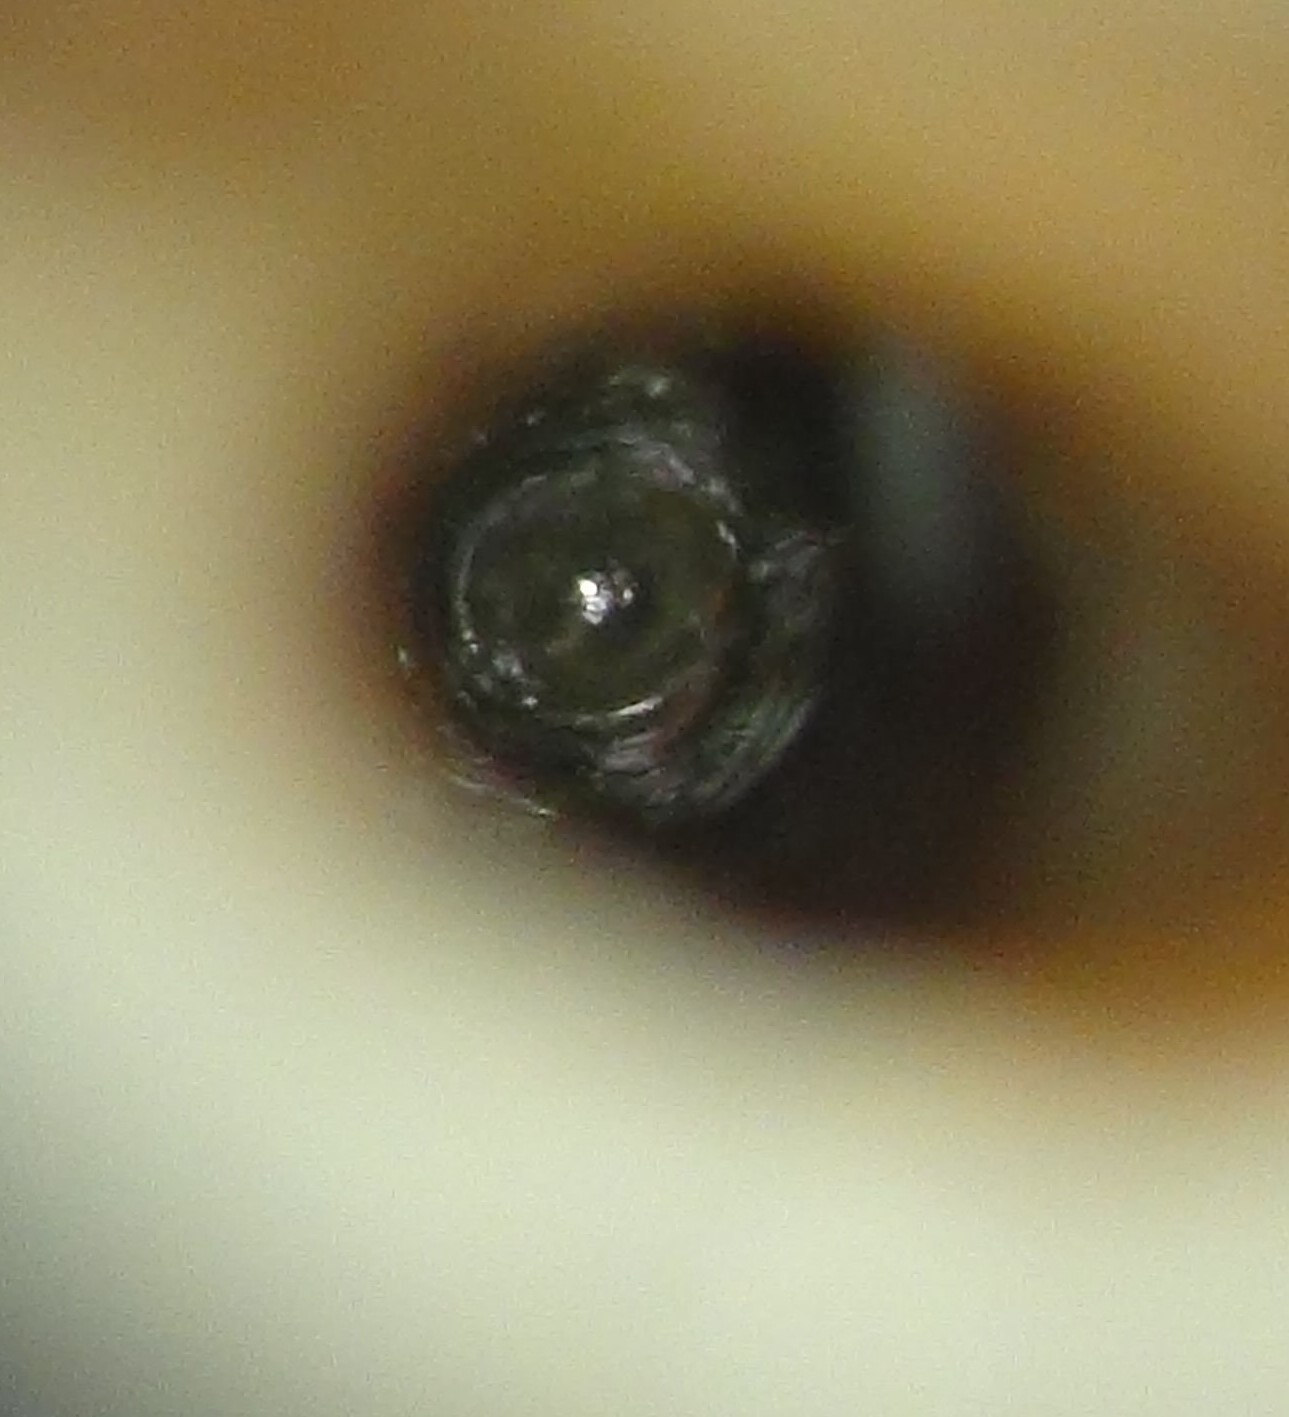

Dus succesvol waren we wel met de kanaalbehandelingen. De afgelopen 8 jaar heeft P. geen pijn meer gehad, tot 2 weken geleden. Er lijkt iets aan de hand met de apex 21. Die apex lijkt iets korter of in ieder geval iets anders dan op de foto’s uit 2006 en 2010. Zou herinfectie een rol hebben kunnen spelen? Ondenkbaar is dat niet. Composiet vullingen lekken vanaf dag 1 en gutta percha kan niet zo goed weerstand bieden tegen lekkage. De foto genomen door de microscoop van het palatinale aspect van element 21 doet vermoeden dat er zeker sprake moet zijn van lekkage.